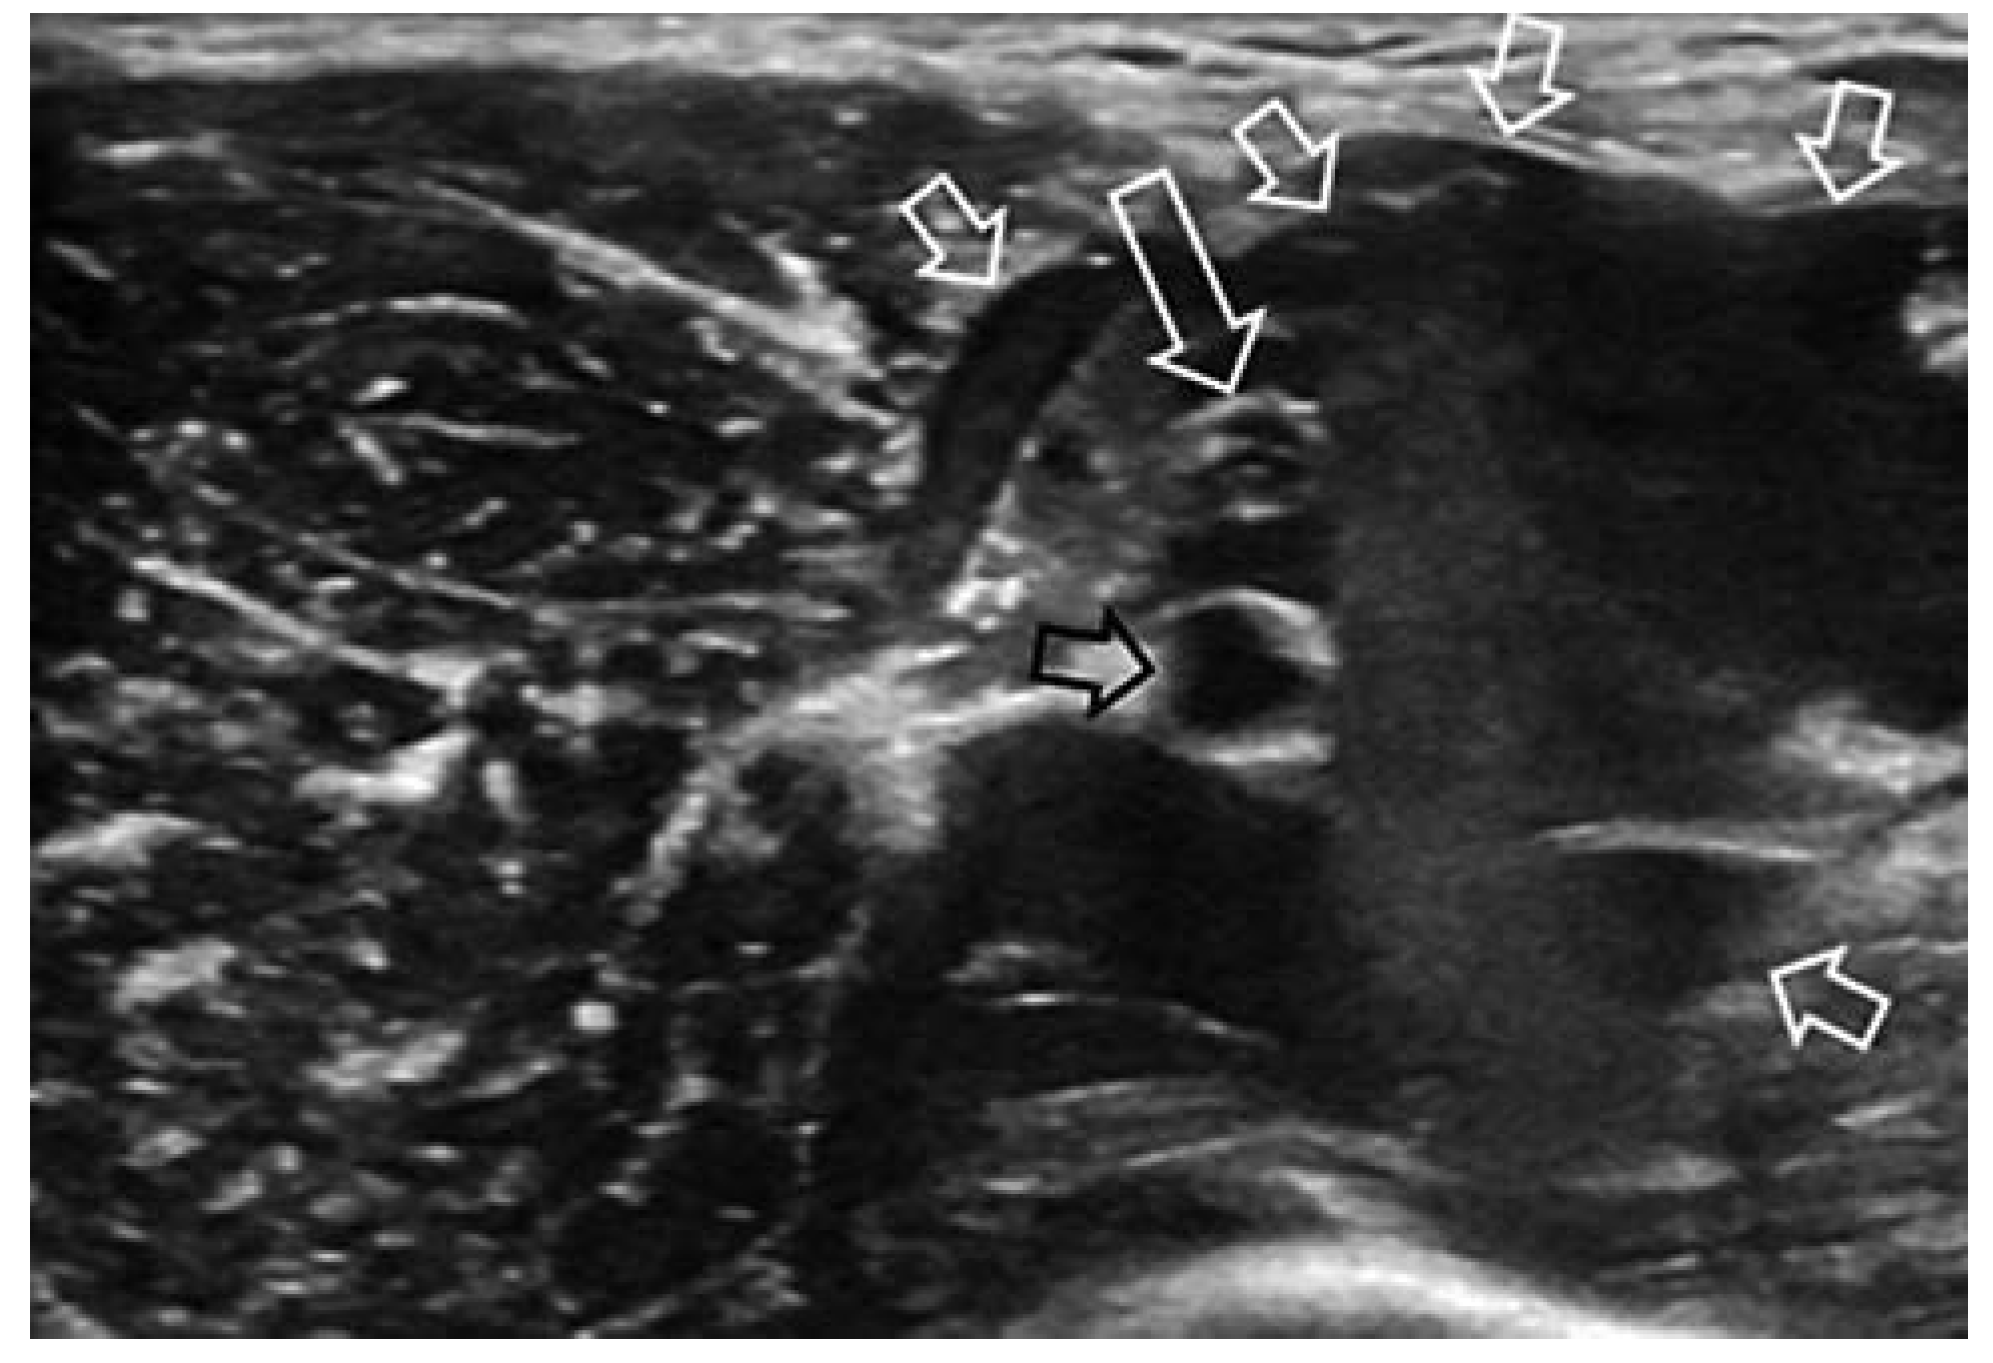

Venöse Malformationen

Lymphatische Malformation

Arteriovenöse Malformation